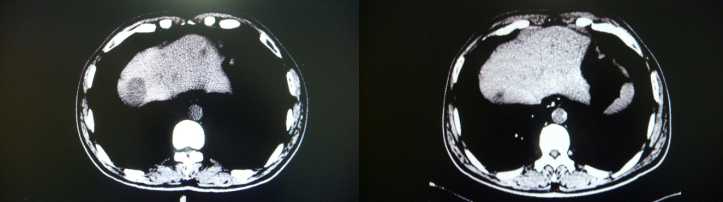

结果: 腹部CT检查,与回输前2005-11-15腹部CT结果相比较: 可见肝S4结节低密度结节较前缩小(20mm×13mm→18×12mm) 肝右叶低密度结节较前缩小(16mm×24mm→14mm×22mm), 脏壁层腹膜表面及肠管表面多发结节较前缩小(20mmX22mm→17mmX1 5 mm ) 双侧附件区及盆腔内腹膜多发异常强化结节及肿块亦较前缩小,现最大75mm×60mm,原为95mm×60mm。 腹水较前减少。